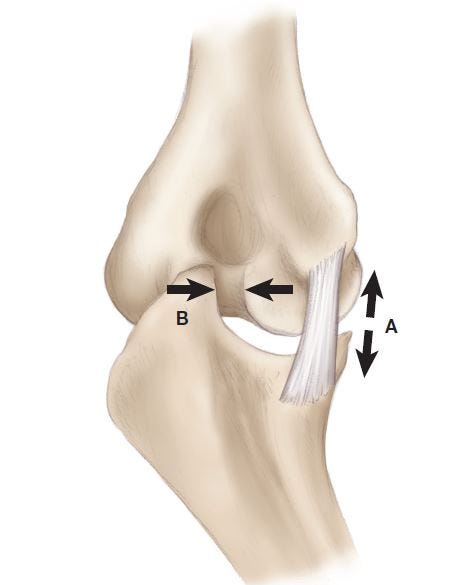

First, hard throwers, including pitchers and position players, not only impose great force on their UCL, but they also put great force on the bone at the back of the elbow, called the olecranon (Figure 1). This additional stress can create bone spurs, also called osteophytes. Similar to how stress on the skin, such as to your hand with batting, can cause skin callous. The bone spurs can crack and become loose, which is often referred to as “chips in the elbow” (Medically, bone chips are referred to as loose bodies). When the bone spurs break, they can cause significant pain in the back of the elbow. Because the location of the pain is near the triceps tendon, many players incorrectly believe they have triceps tendinitis.

We’ve observed a relationship between bone chips that form in a thrower’s arm, and injury to the UCL. For some players, an injury to the UCL may have occurred, and the slightly stretched ligament will result in the olecranon bone having to absorb compounding stress with each throw. I was able to prove this during a research study over 10 years ago, and leverage that knowledge today to perform careful examinations of every player’s UCL who has a bone chip in their elbow. Not every examination requires an MRI, but it’s important to know when you absolutely do.